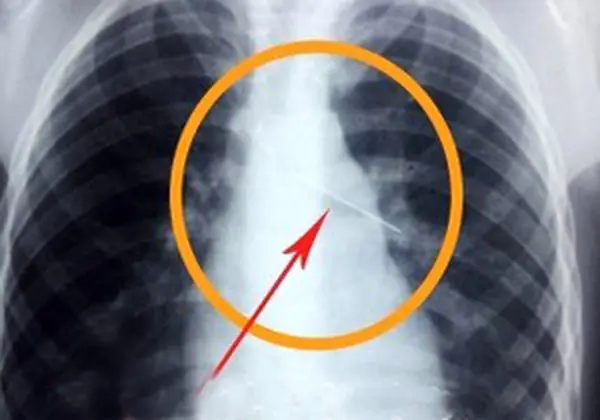

دختر اهوازی سر کلاس سوزن قورت داد /خانواده وی به مدرسه حمله کردند ! + عکس

رکنا: جزئیات ماجرای دانش آموز اهوازی که سوزن را قورت داد از سوی مدیر روابط عمومی آموزش و پرورش خوزستان تشریح شد.

به گزارش رکنا، بابک نوری زاده مدیر روابط عمومی آموزش و پرورش خوزستان گفت: دانش آموز مدرسه دخترانه دوره اول متوسطه در منطقه «عین دو» آموزش و پرورش ناحیه چهار اهواز وقتی سر کلاس زنگ کاردستی و فناوری، واحد کار خیاطی داشته به معلم اعلام می کند که سوزن قورت دادم و دل درد دارم.

شبکه های اجتماعی در استان خوزستان خبری درباره اجبار معلم یک مدرسه دخترانه به دانش آموز دختر برای بلعیدن سوزن داده اند که باعث خون ریزی دختر نیز شده است. اخبار 24 ساعت گذشته رکنا را از دست ندهید